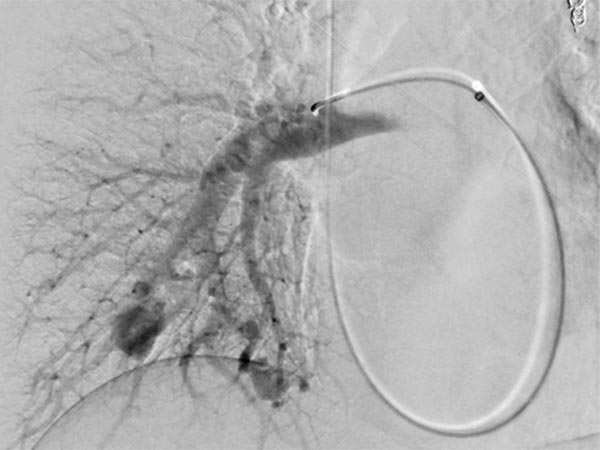

Über das Herz wurde vom Hals (transjugulär) eine Schleuse in die rechte Pulmonalarterie eingebracht, hierüber ein Koaxialkatheter. Nach Injektion von Kontrastmittel zeigen sich auch im rechten Unterlappen Lungenstrombahn pulmonale AVMs.

Nach Sondierung der größeren pulmonalen AVM zeigt sich ebenfalls eine für den Morbus Osler typische Dilatation der direkten arteriovenösen Kommunikation in Form eines Aneurysmas. Der venöse Abstrom ist stark dilatiert, damit ist die Gefahr einer Embolie besonders groß.